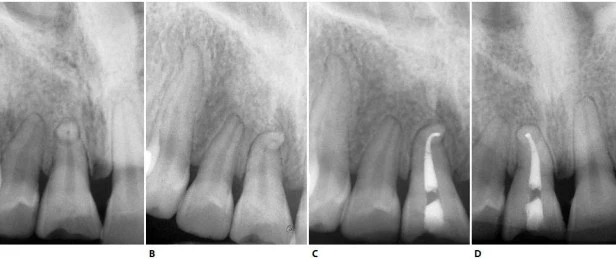

Rất hiếm trường hợp có hai ống tủy trong một chân răng. Tuy nhiên ống tủy đôi khi chia ra ở đoạn gần chóp tạo hai ống tủy nhỏ (Weine’s type IV) (hình 11.35). Ống tủy phụ được tìm thấy ở nhiều vị trí khác nhau trên chân răng và tỉ lệ có ống tủy phụ là rất cao(hình 11.36 A, B). Thông thường, có một ống tủy phụ lớn phân nhánh về phía gần và tạo một góc 900 với hướng của ống tủy chính (hình 11.36 C, D).

Hình 11.36. A. Phim trong lúc điều trị ở răng #21. B. 12 tháng sau.Chú ý hình ảnh sự lành thương, ba ống tủy phụ đã được trám, 1 ở gần chóp và 2 cái còn lại ở 1/3 giữa và đều ở phía gần. C. Răng #21 với một ống tủy phụ lớn ở 1/3 chóp. Ống tủy phụ ở phía gần và tạo một góc 900 với ống tủy chính. D. Răng #11 với ống tủy phụ nằm gần lỗ chóp và 1 cái lớn hơn ở 1/3 giữa phía gần và tạo góc 900 với ống tủy chính.